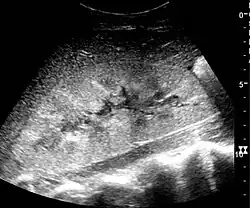

In medical imaging, the acute changes in the kidney are often examined with renal ultrasonography as the first-line modality, where CT scan and magnetic resonance imaging (MRI) are used for the follow-up examinations and when US fails to demonstrate abnormalities. In evaluation of the acute changes in the kidney, the echogenicity of the renal structures, the delineation of the kidney, the renal vascularity, kidney size and focal abnormalities are observed.[20] CT is preferred in renal traumas, but US is used for follow-up, especially in the patients suspected for the formation of urinomas. A CT scan of the abdomen will also demonstrate bladder distension or hydronephrosis.[21]

Renal ultrasonograph of acute pyelonephritis with increased cortical echogenicity and blurred delineation of the upper pole[20] -